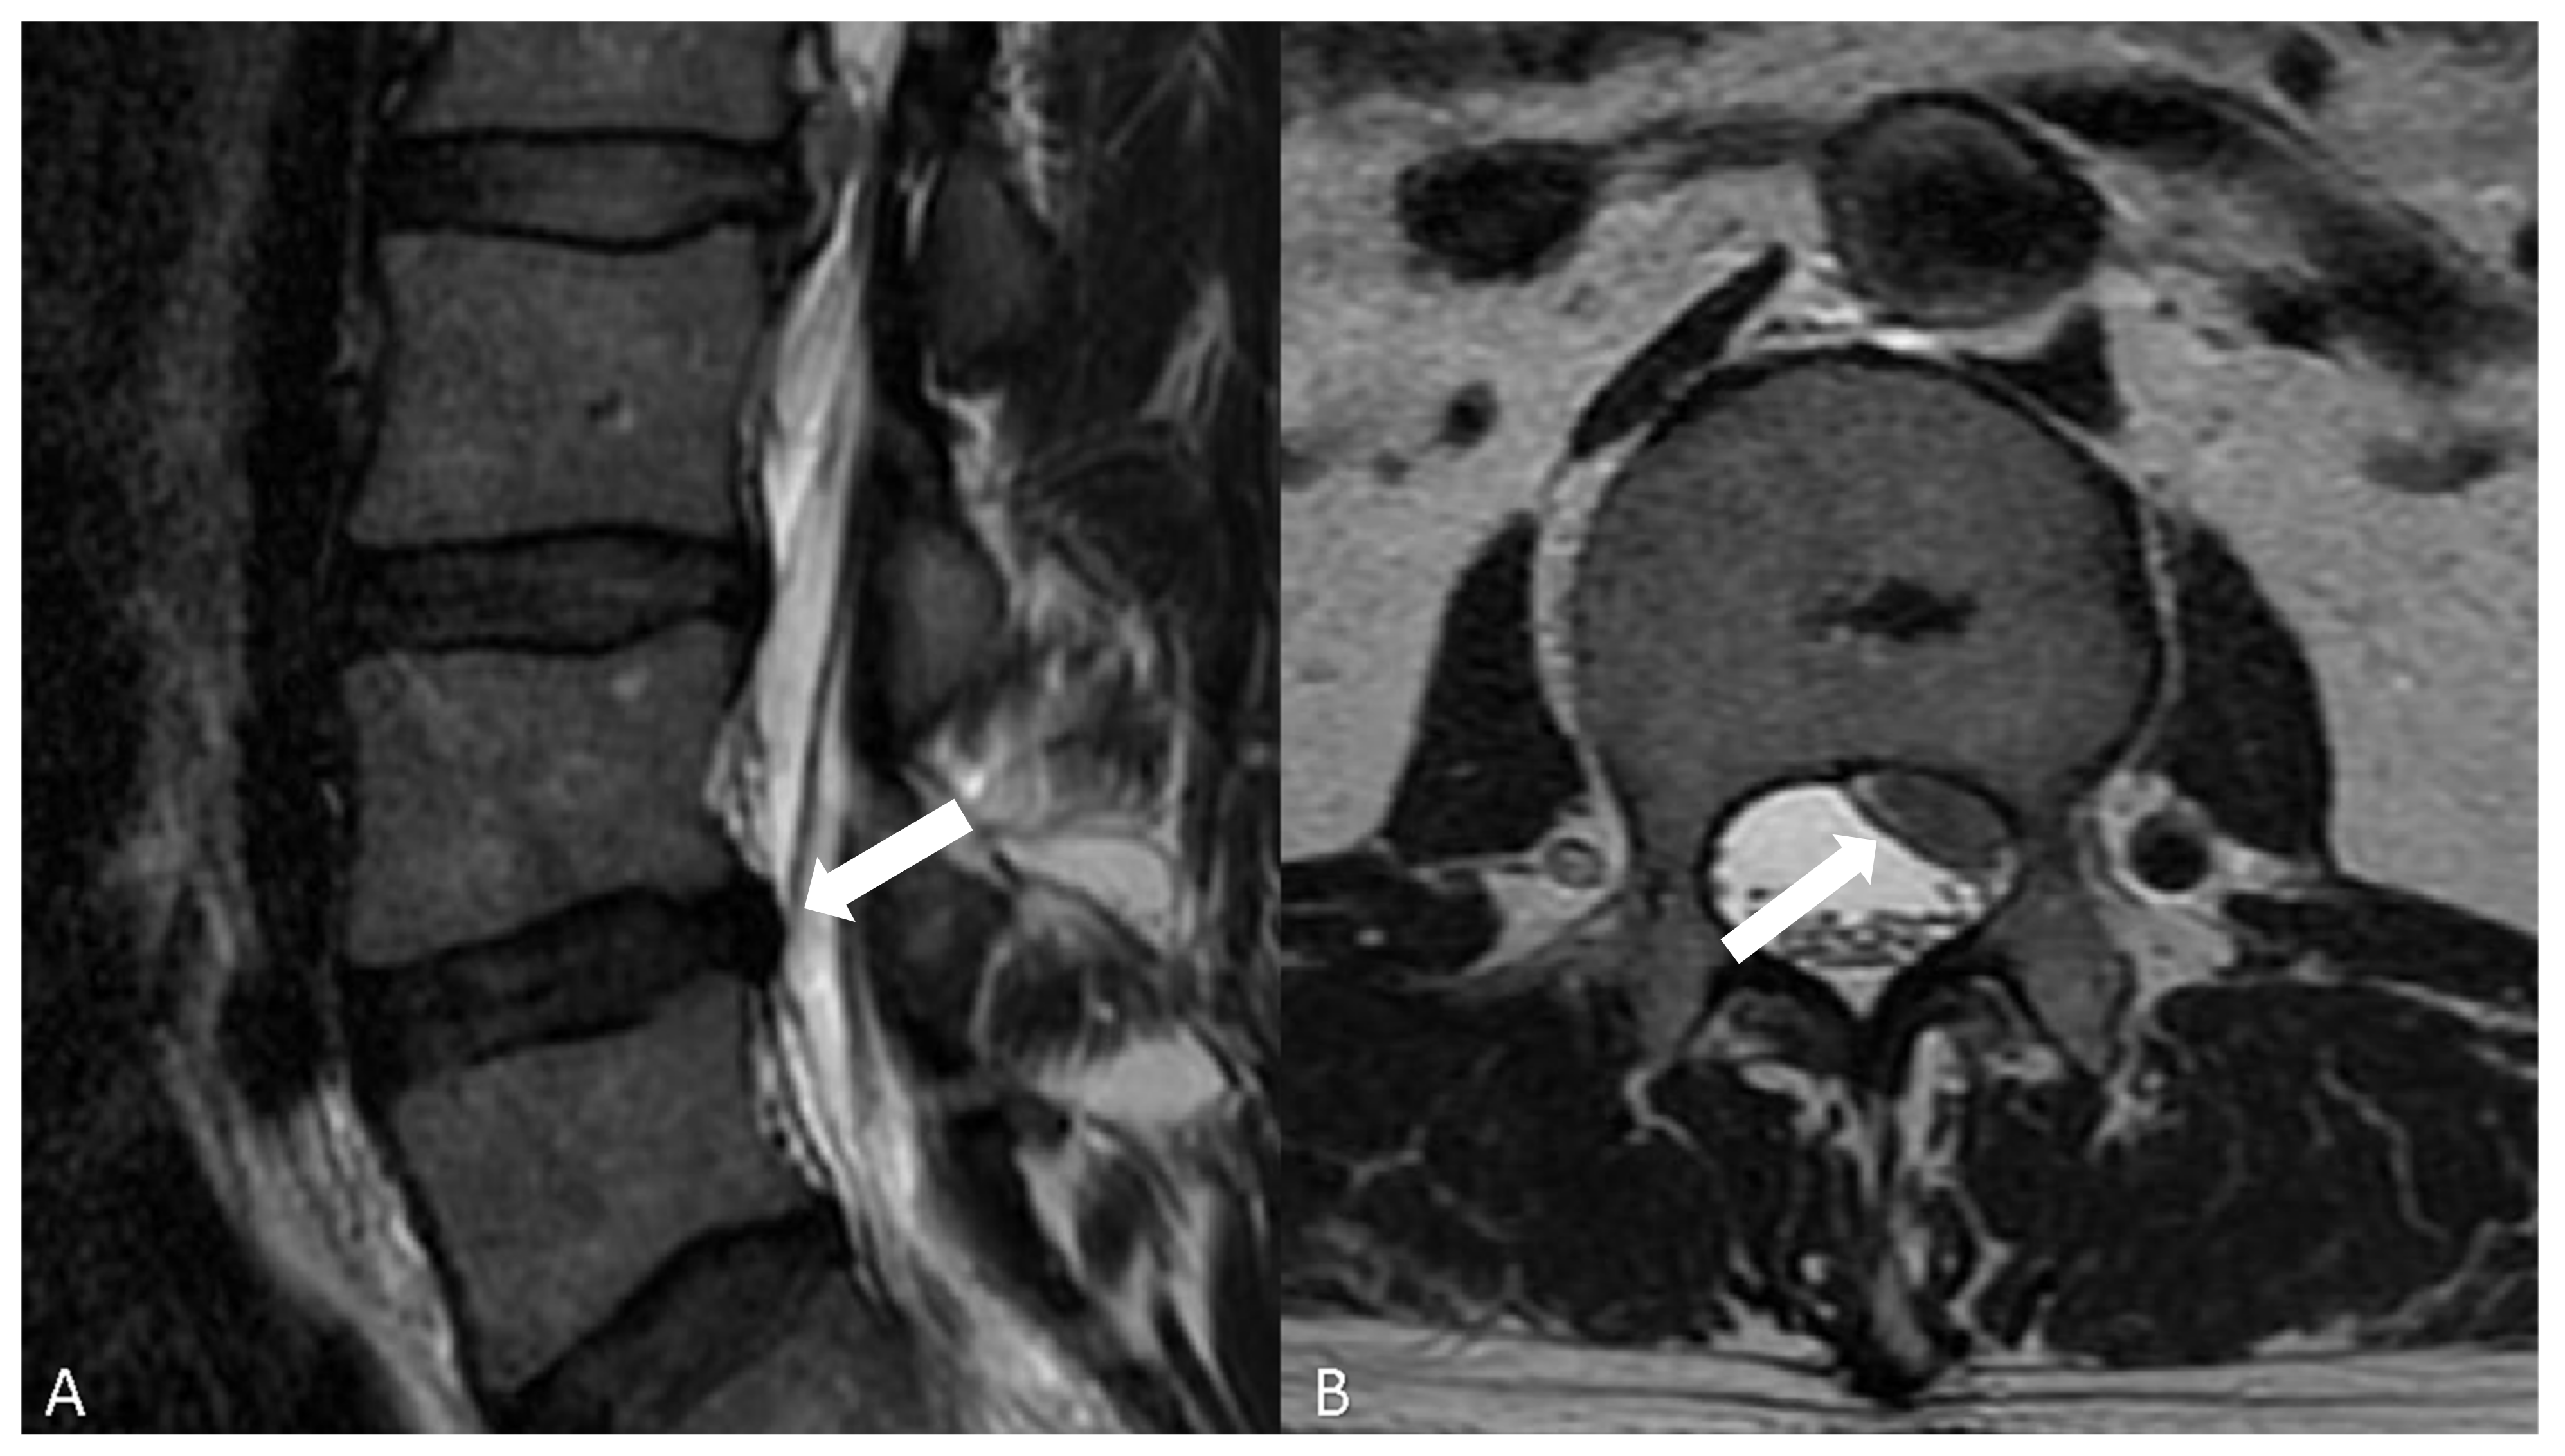

- Modic classification [16] is a classification for vertebral end plates and adjacent vertebral bodies MRI signal modifications secondary to disc inflammation and degenerative disc disease. Modic type 1 refers to decreased signal intensity on T1-weighted images and increased signal intensity on T2-weighted images. Such modifications may be chronic or acute and reflect the penetration of the end plate by fibrovascular tissue, inflammatory changes, and edema. Modic type II refers to increased signal intensity on T1-weighted images and isointense or increased signal intensity on T2-weighted images, indicating replacement of normal bone marrow by fat. Modic type III refers to decreased signal intensity on both T1- and T2-weighted images, indicating reactive osteosclerosis [55] (Figure 4).

| Type | T1 | T2 | Histopathology |

|---|---|---|---|

| 1 | Hypointense | Hyperintense | Bone marrow edema |

| 2 | Hyperintense | Hypointense | Fatty replacement |

| 3 | Hypointense | Hypointense | Sclerosis |